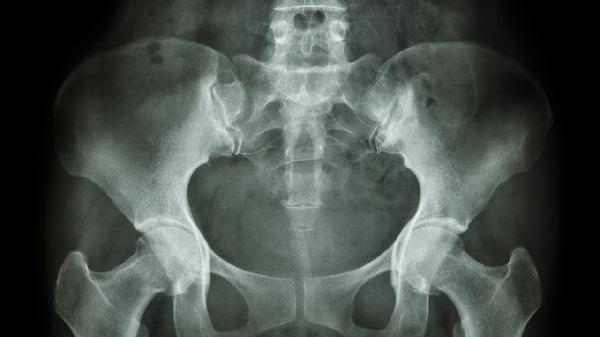

耻骨突出可通过物理治疗、药物治疗、手术治疗等方式改善,具体需根据病因选择。耻骨突出可能与外伤、先天发育异常、骨质疏松、骨盆炎症、妊娠分娩等因素有关。

严重耻骨联合分离超过10毫米或合并骨盆骨折时,需行耻骨联合内固定术。先天性骨盆畸形可采用截骨矫形术,术后需配合牵引治疗。所有手术方案需通过CT三维重建评估,术后严格卧床6-8周。